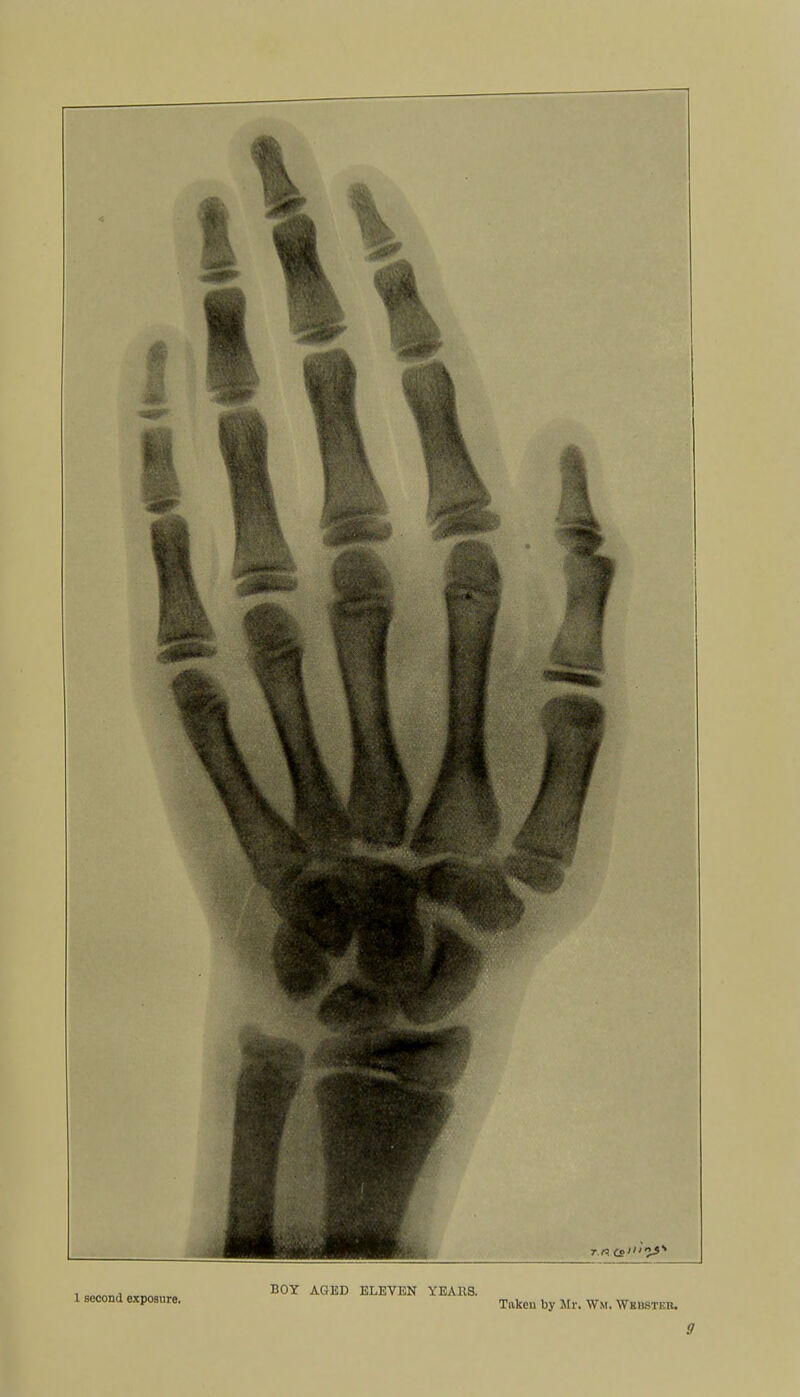

Skiagraphic atlas showing the development of the bones of the wrist and hand : for the use of students and others / by John Poland.

- 1898